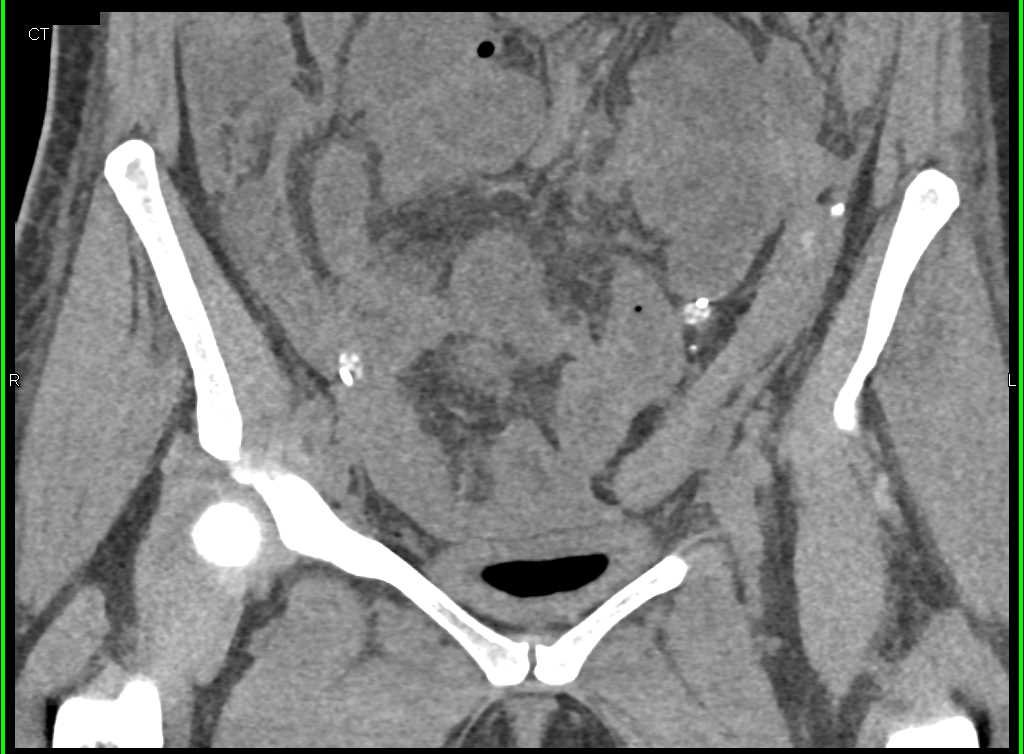

Extravasation from the Bladder